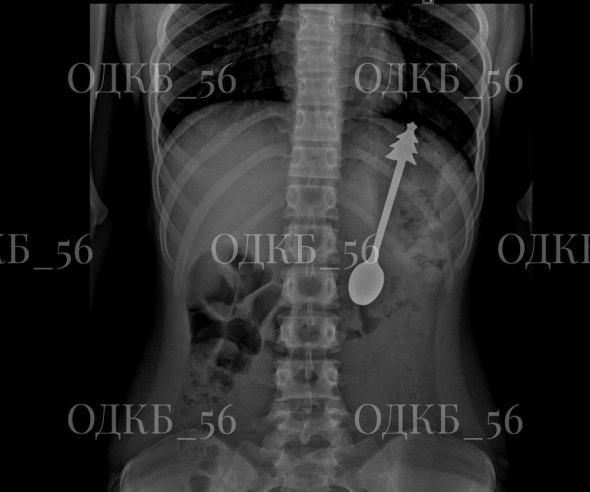

В Оренбурге в больницу попал ребенок, который случайно проглотил металлическую ложку длиной 14 сантиметров. Маленького пациента в экстренном порядке доставили в Оренбургскую областную детскую клиническую больницу.

Рентген показал, что инородный предмет находится в желудке. Ребенка госпитализировали в детское хирургическое отделение, где было принято решение о проведении эндоскопического вмешательства.

Ложка, которую достали из ребенка. Фото: ОДКБ

Ложку удалось извлечь без осложнений. Уже на следующий день ребенка выписали домой, его состояние оценивается как удовлетворительное.